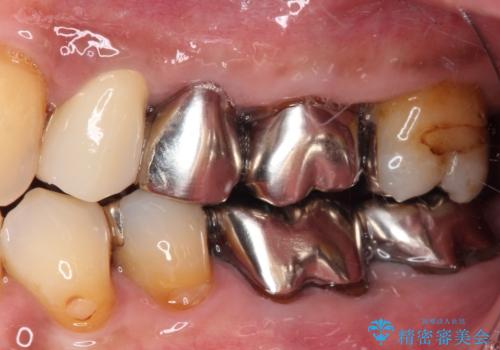

- 詰め物が欠けてしまい、虫歯かもしれないから診てほしいとのことで来院された患者様です。

精査の結果、詰め物の下に虫歯が大きく広がっているのがわかりました。

虫歯の範囲が大きく、部分的な詰め物では対応が難しいため、オールセラミッククラウンにて補綴することとしました。